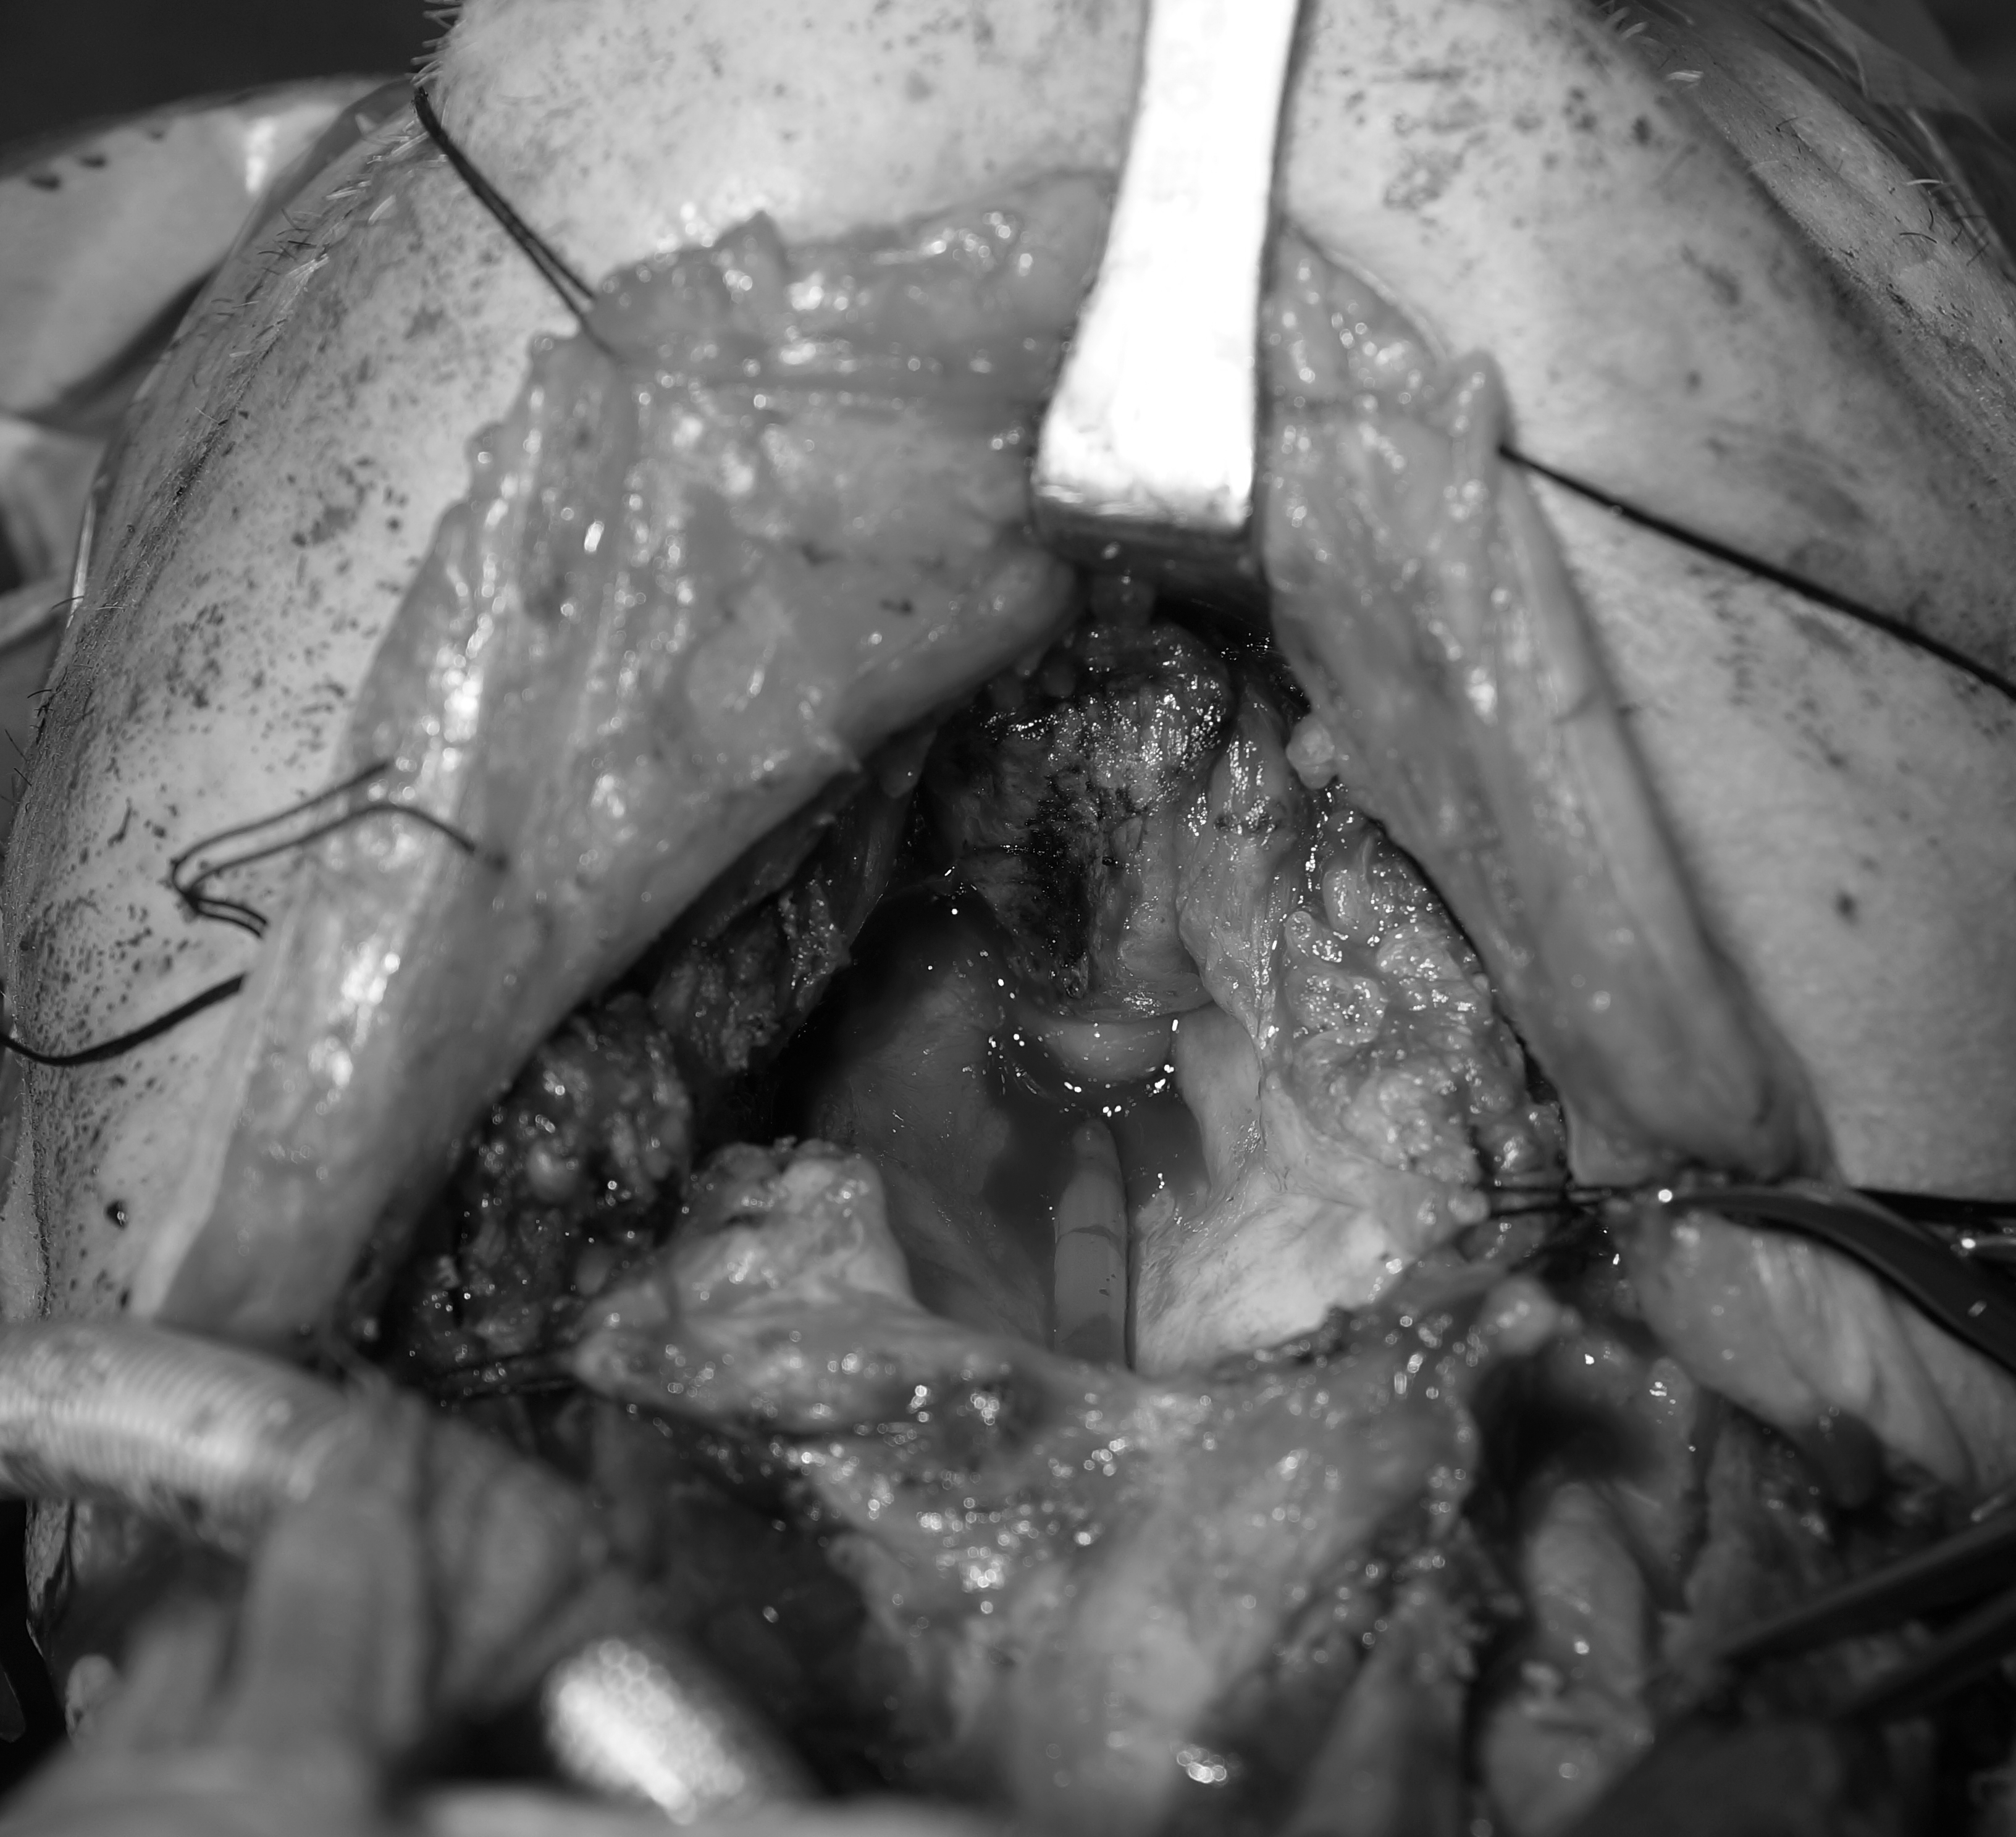

그간 스마트폰을 이용해서 수술장 사진 촬영, 수술 검체 사진 촬영을 주로 해왔고, 나름 잘 사용하고 있었지만 간간히 발생하는 문제들 – 수술 부위가 깊고 작은 경우 정확한 초점잡기도 어려울 뿐 더러 접사 촬영을 위해서는 카메라를 수술 필드 안으로 가져와야하는데 멸균된 비닐로 감싸고 하는 과정들이 쉽지 않은 상황이었습니다. 특히나 작년 이직 후 수술장 검체 및 수술 부위 사진을 촬영하는 환자들이 늘어나면서, 더욱 제대로된 촬영에 대한 욕심이 생겼습니다.

카메라로 뭐를 찍을 것이냐라는 측면에서 본다면, 구강암 환자 촬영을 위해 구강, 치아에 대한 촬영 뿐 아니라 수술 검체, 경부의 수술 필드에 대한 촬영이 모두 필요했습니다. 덤으로, 이 때 구입하는 렌즈를 개인적인 취미 용도로도 활용 가능하다고 생각하고 브랜드를 결정해야하 했습니다.

수술 필드의 각 구조물이 전체적으로 보여져야하는 경우에는 얕은 심도는 필요가 없기 때문에, 오히려 F8 정도로 조리개를 조여줘야 합니다. 이에 따른 플래쉬(flash)구입이 필수라고 봐야겠고요.